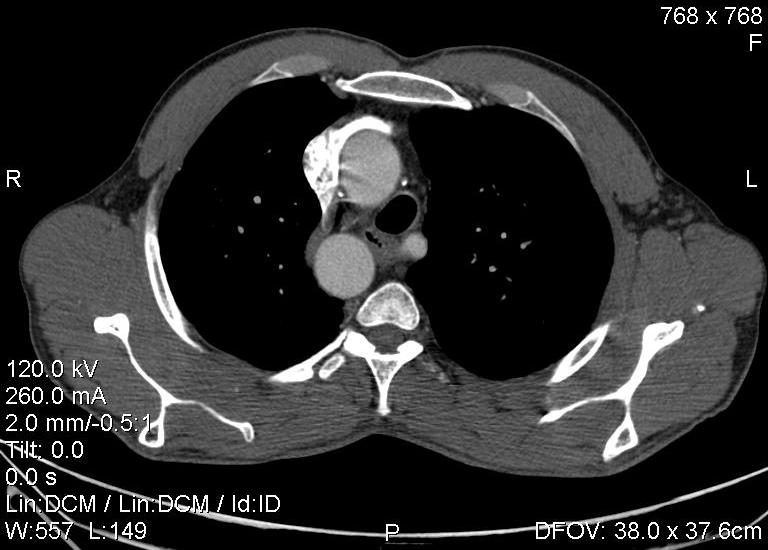

Пациент был направлен на КТ после рентгенографии ОГК, с направительным диагнозом: объёмное образование верхнего средостения.

это аномально расположенная грудная аорта

Конечно, дуга аорты идёт справа от позвоночника (декстра позиция); но есть и ещё одна аномалия той же группы: